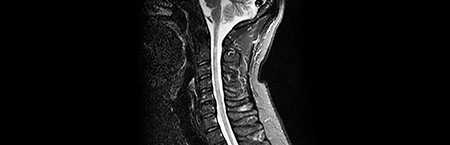

• Ressonância magnética do neuroeixo

Ressonância magnética

• Carga lesional extensa

• Inúmeras novas lesões em relação a RM prévia

• Ressonância magnética

• "aumento do número de lesões supratentoriais (…) no estudo medular não se destacam seguras lesões de novo"

• Ressonância magnética de rebaselining 6m após início de terapêutica

• Apresentava estabilidade da carga lesional supratentorial, e ausência de lesões captantes

• Referência a nova lesão em D6